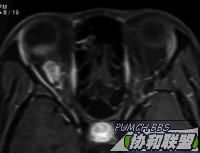

增强

图片点击可在新窗口打开查看